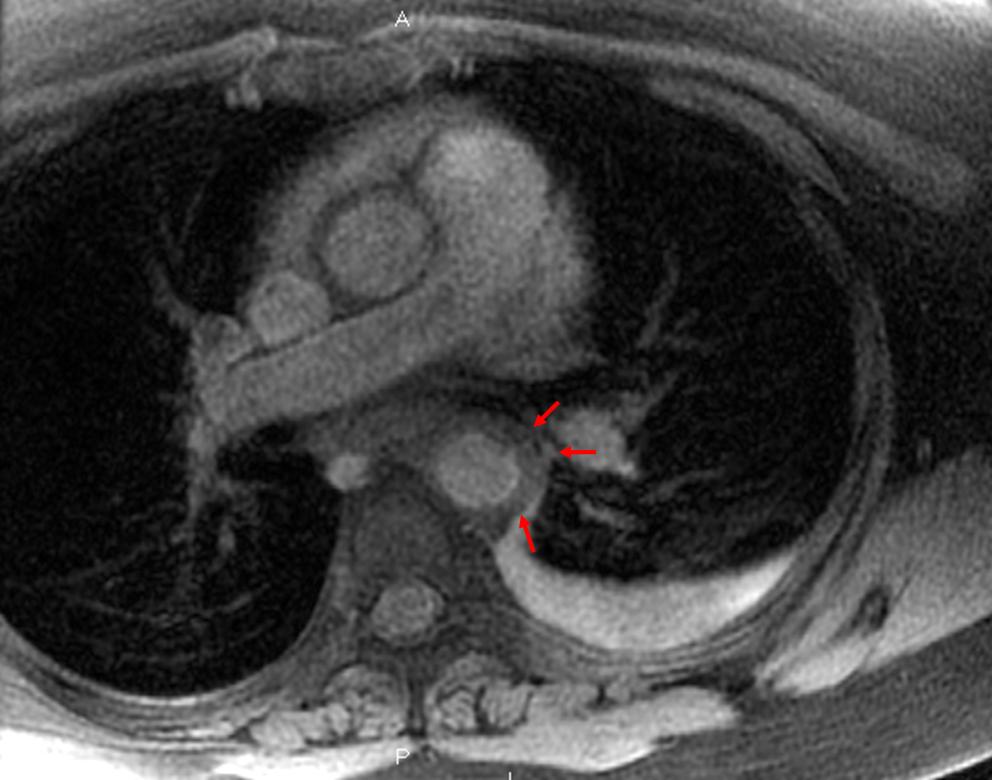

Aortic Dissection In Patients With Bicuspid Aortic Valve ...

Found to have a bicuspid aortic valve and had cross-sectional computed tomography (CT) or magnetic reso-nance imaging (MRI) studies available for analysis. ... Content Retrieval